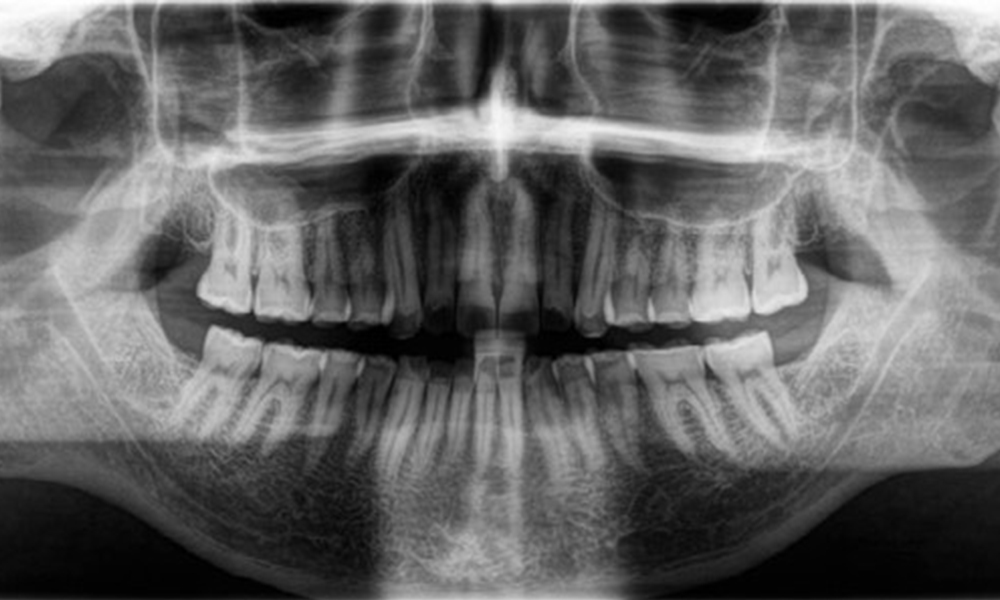

Résultats radiologiques

Une denture adulte complète, sans carie ni perte osseuse radiologiquement reconnaissable, a été observée (Fig. 6). La perte radiologique d'émail et de cuspides était particulièrement évidente sur les 36 et 37.